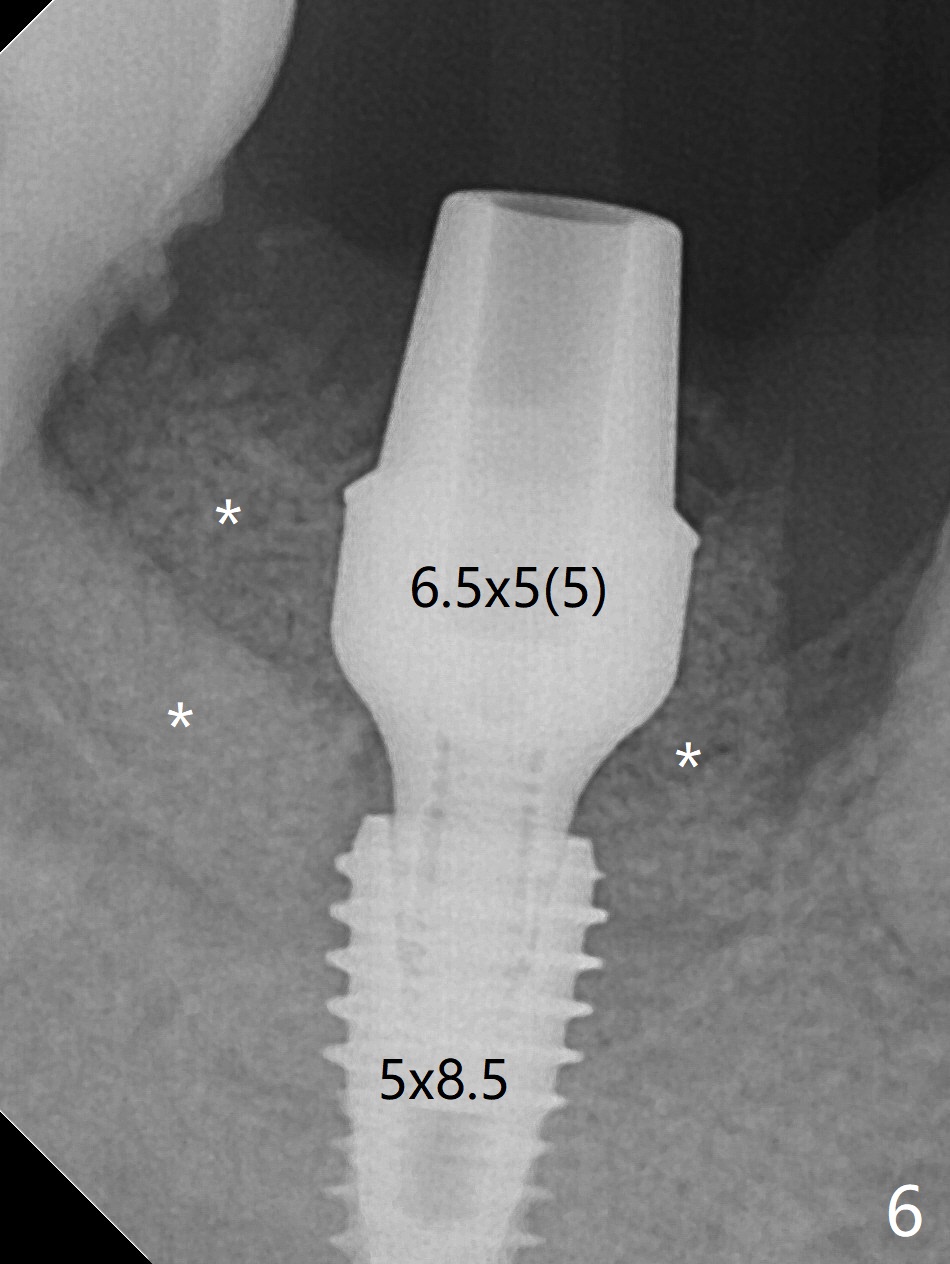

The affected tooth (#31, Fig.1) has severe buccal gingival recession with mobility III. After extraction and removal of granulation tissue, osteotomy is initiated in the middle of the fused socket using IS drills with 4 mm stopper (Fig.2,3). Following sequential osteotomy until 4 mm drill, a 4.5x10 mm IS dummy implant does not achieve primary stability, whereas 5x10 mm one does (Fig.4,5). Due to limited bone height confirmed intraoperatively, a shorter UF implant is placed with insertion torque 30 Ncm (Fig.6,7) with ~ 4.5 mm implant threads exposed coronally. After placing a 6.5x5(5) mm abutment, Vanilla Graft (*) and PRF membrane and collagen plug, an immediate provisional is fabricated to close the remaining socket. The tooth #32 is kept initially to increase the stability of the provisional and removed 8 day postop because of discomfort. A 5.5(2.5) mm mill abutment is changed to 3 months postop. The implant seems ready for impression 6 months postop (Fig.8). The bone graft remains around the apical portion of the mill abutment with apparently new bone formation around the coronal portion of the implant10 months postop (Fig.9); porcelain (*) has been added to close the mesial gingival embrasure and proximal contact gap. Due to unfavorable crown/implant ratio and poor trajectory, the crown/abutment becomes loose once post 1st cementation. Guided surgery would avoid the trajectory isssue.